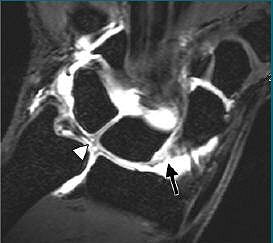

![]() |

| Above, posteroanterior radiograph of wrist in neutral position shows no evidence of scapholunate dissociation or carpal instability; alignment of both carpal rows is preserved. Below, conventional midcarpal arthrographic image of same wrist shows SLL (arrow) and central TFC (arrowhead) tears. |

| Coronal 3D dual-echo steady-state MR image (60/10, 20˚ flip angle) findings in same wrist (as above) confirm presence of volar SLL (arrow) and central TFC (arrowhead) tears. "Association Between Extrinsic and Intrinsic Carpal Ligament Injuries at MR Arthrography and Carpal Instability at Radiography: Initial Observations," Theumann NH, et al. Radiology 2006;238:950-957. |

The authors noted that all intrinsic ligament tears seen at MR arthrography were confirmed in the 28 patients who also underwent arthroscopy. However, no extrinsic ligament tears were seen with arthroscopy. All extrinsic ligaments lesions were complete tears. There was a significant correlation between SLL tears LTL tears with carpal instability on x-ray, the authors added.